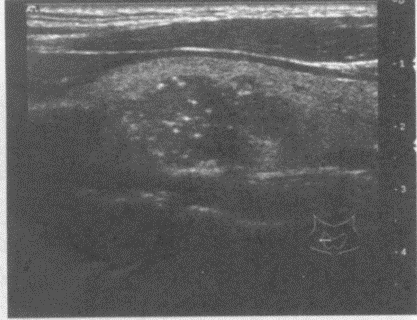

4、单项选择题

患者,女性,甲状腺肿大。探及多个结节状的强回声光团,其内可见暗区。如图所示,最可能的诊断为()。

A.甲状腺功能亢进

B.甲状腺腺瘤

C.甲状腺炎

D.结节性甲状腺肿

E.甲状腺癌

5、单项选择题 结节性甲状腺肿最常见的原因是()。